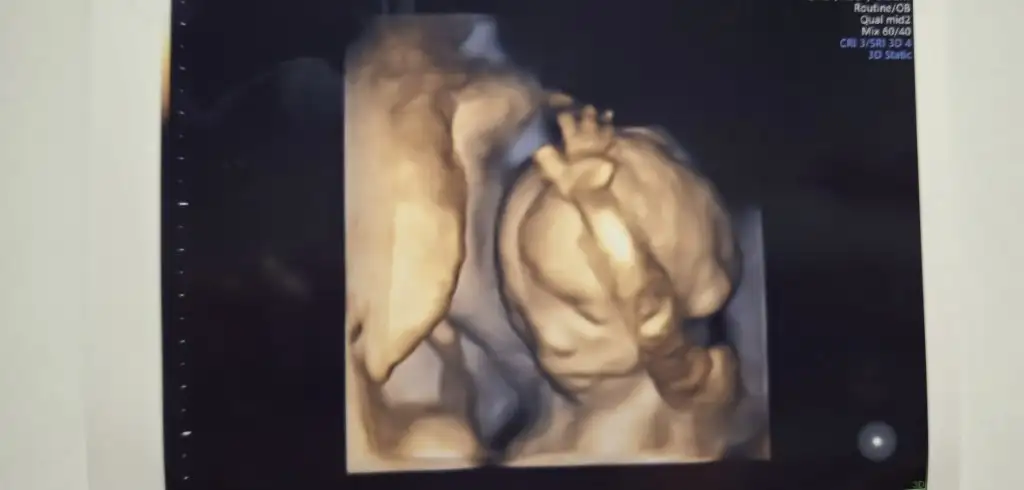

SüphanAllah maşallah Rabbim sen nelere kadirsinHerkese merhaba bizim de bugün kontrolümüz vardı.Giderken çikolata kahve muz filan yedim hareket etsin diye. Gittiğimizde hareket etmiyordu sonra birden ben burdayim der gibi elini kaldırdıBu arada o pıt pıt atışları 14+5 günlükken hisetmeye başladım bence de o hareketler bebek şu an 18. haftadayız özellikle yemekten ve tatlıdan sonra hemen hissediliyor ve ilk bebek olmasına rağmen Eki Görüntüle 3459277